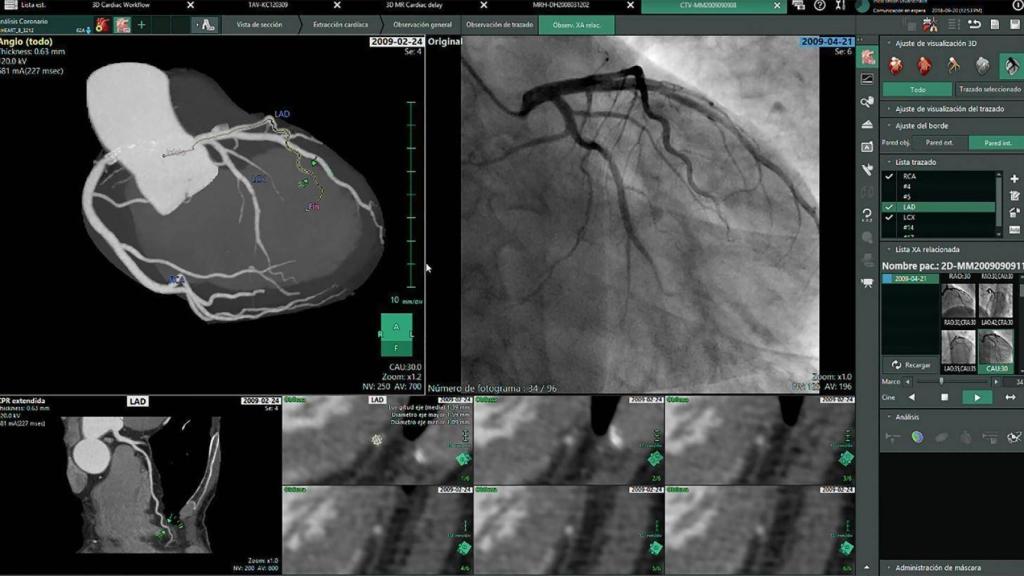

Nueva fase de Ykonos y 13 millones de euros

El SESCAM se encuentra en este momento en pleno desarrollo de la VII fase del Proyecto ‘Ykonos’, a la que el Gobierno regional va a destinar una inversión de 13 millones de euros durante los próximos cuatro años. De este modo, en esta nueva fase se van a añadir soluciones avanzadas de diagnóstico radiológico (reconstrucciones 3D y 4D, medición de volumen, fusión de estudios, extracciones de vasos o funciones de medición e informado), al tiempo que se van a incorporar todos los estudios de señales e imágenes del resto de especialidades (fondos de ojo, endoscopias, electrocardiogramas o ‘holter’) y se va a crear la carpeta dosimétrica del paciente.